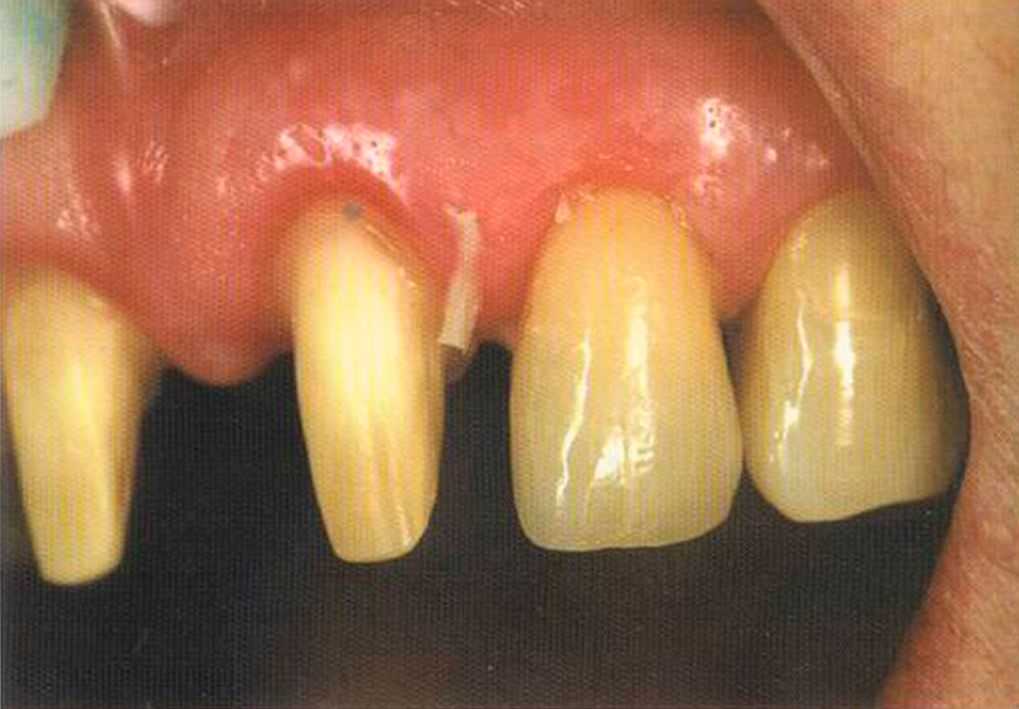

Этот пациент — португалец. Он всю жизнь имел такое положение зубов. Небнорасположенный боковой резец теперь необходимо удалить, а затем воссоздать как эстетику, так и функцию в области фронтальной группы зубов. Планируется изготовить коронки In-Ceram в области 11 и 21 и соединить их вместе из-за увеличивающейся подвижности зубов.

Препарирование, проводимое доктором Риссе, оценивается как очень сложное. Режущие края центральных резцов сильно дивергируют, что создает неудобство при формировании хорошего уступа.

Фото сверху и слева: отличный результат препарирования зубов с уже уложенными нитями для снятия оттиска.